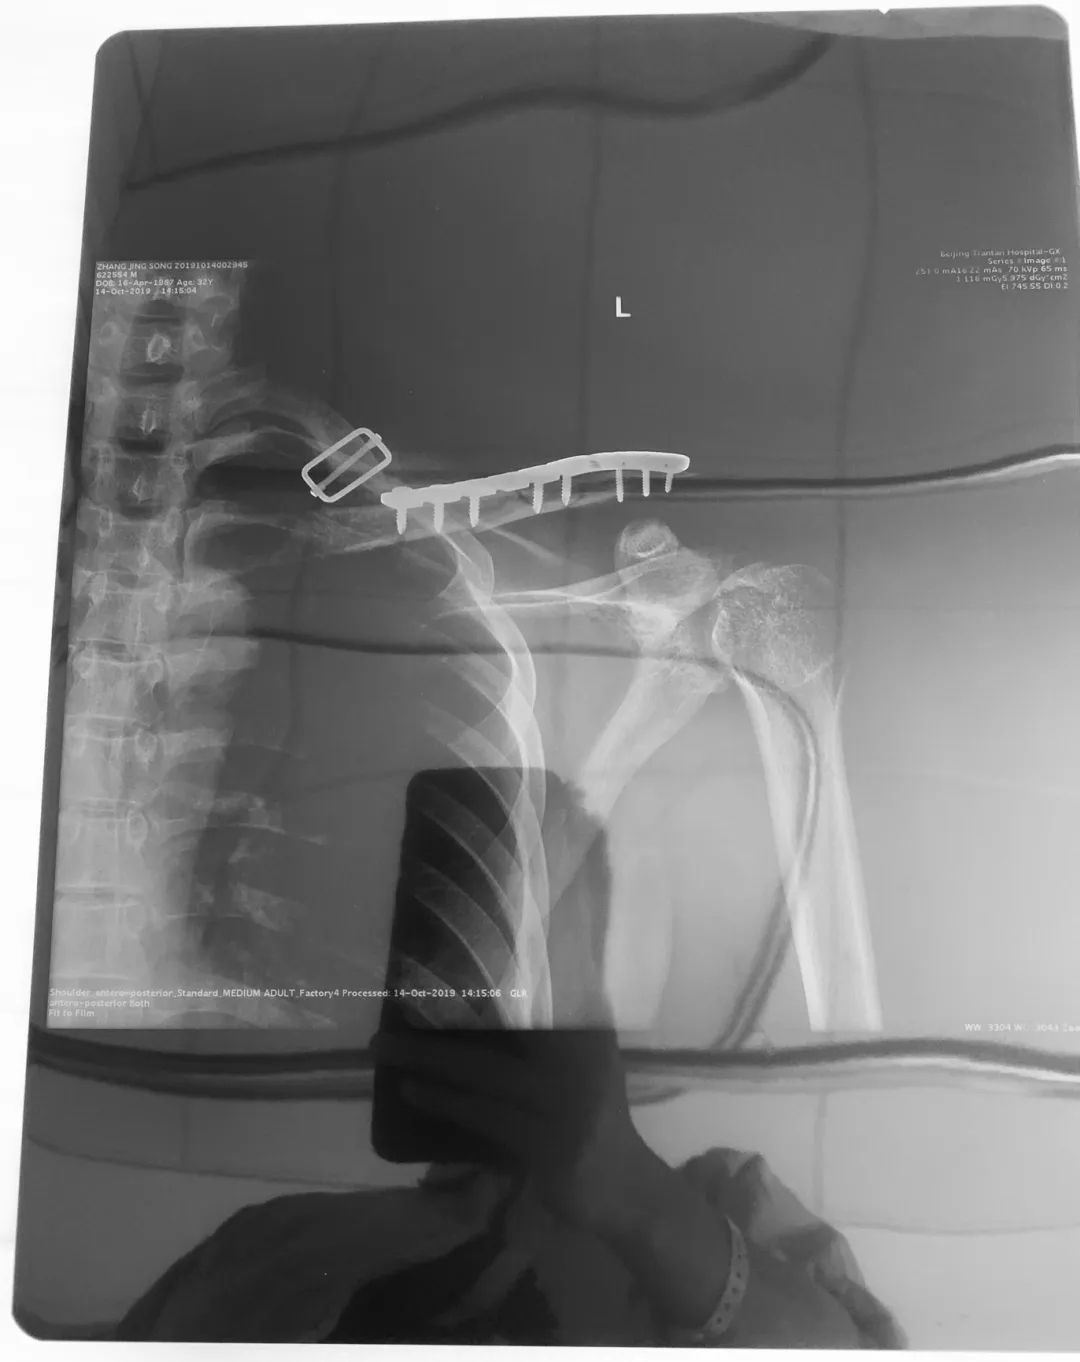

锁骨上的钢板和钢钉丨作者供图

回顾这次受伤,住院七天,抽过两次血,扎过两针输液,一道刀口缝了十针。虽然对真正的手术过程一无所知,但我知道在左肩那片敷料盖住的地方,皮肉之下多了一块钢板和九颗钢钉。万一未来的考古学家挖出我完整的锁骨,会不会觉着是一根笛子。